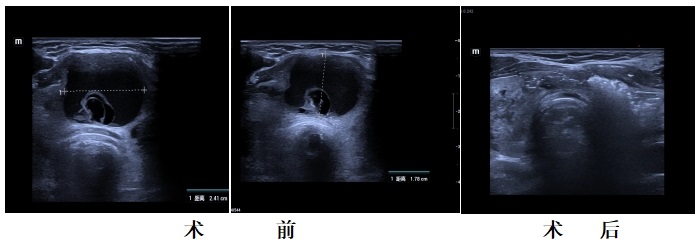

近期,我院肝胆外科成功为多例甲状腺囊肿患者实施了超声引导下酒精硬化治疗,均取得了较好的治疗效果。

1.精准定位:在超声实时引导下,医生用细针穿刺囊肿,抽吸囊液。

2.注入酒精:将无水酒精注入囊腔,使囊壁细胞凝固、坏死,从而有效防止囊肿复发。

3.快速恢复:术后仅留微小针眼,无需缝合,观察片刻即可离院。